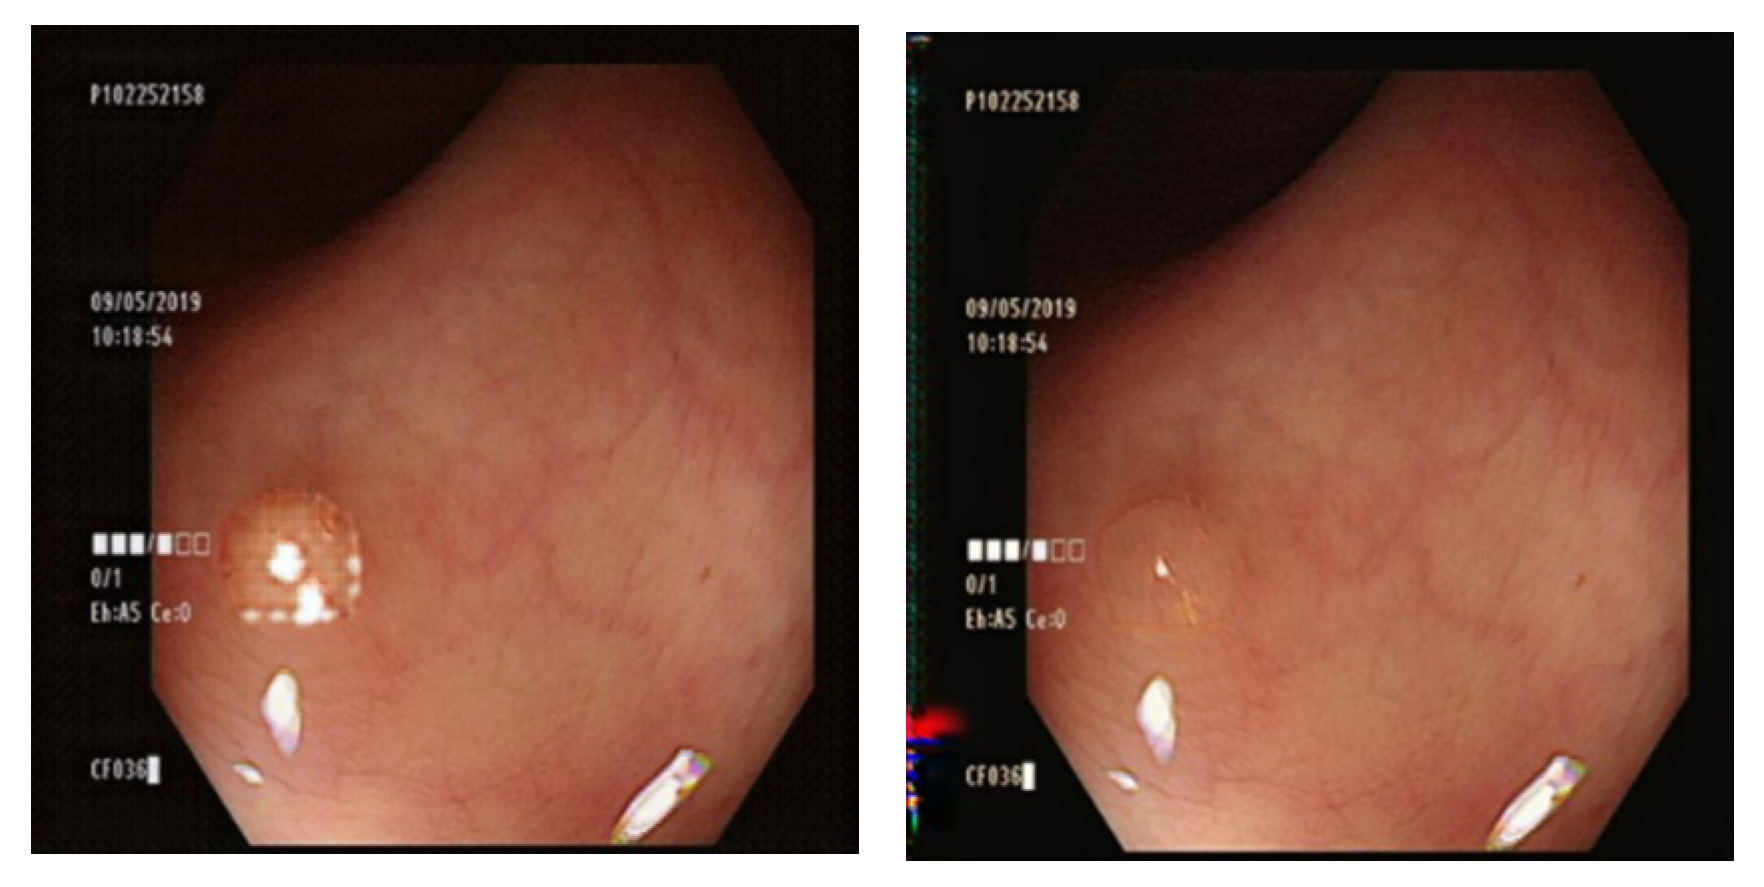

3.7. Comparison of GAN Output

4.1. Comparison of GAN-Generated Images